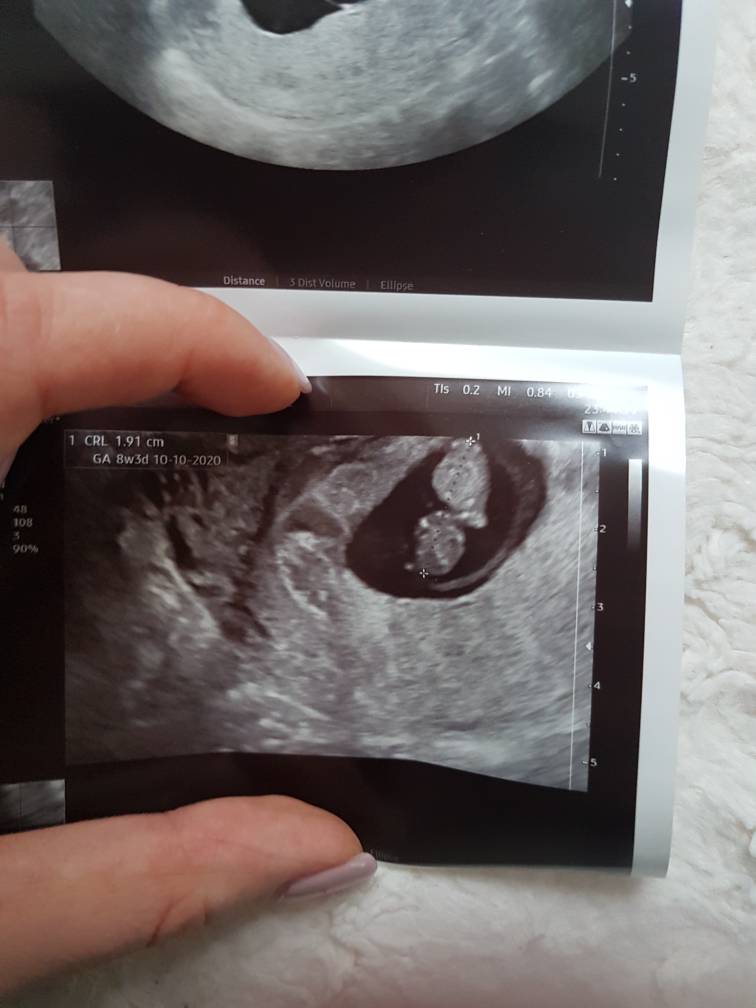

A ja wróciłam od mojej miejscowej dr z usg. Z dzidzia wszystko ok, pokazała.mi główkę, Zawiazke raczek i nożek[emoji173] pokazała serduszko ale nie włączyła bo powiedziała, ze nie wolno za często zeby "nie zagotować ". Na plamienia powiedziała,ze dobrze ze brązowe. Jest tam krwiak ale ona mówi,że widac,że się dalej nie rozwarstwia. Z usg jednego 8t3d z drugiego 8t1d.. mowi,ze zależy jak się zmierzy.

Wrzucam nasza fasoleczke